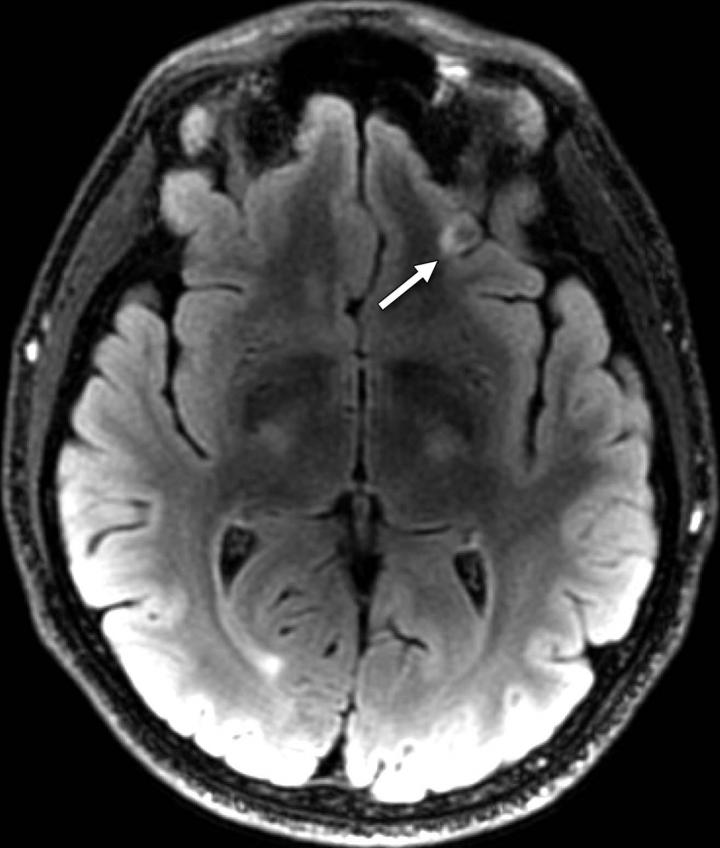

Smoking may cause white scars on the brain What Are Scars On The Brain The size, location, and appearance of the scar may vary depending on the area of the brain affected and the type of. Brain aneurysm surgery may cause a scar at the incision site. Brain lesions can be caused by injury, infection, exposure to certain chemicals, problems with the immune system, and more. This is known as gliosis. Controlled scar formation. What Are Scars On The Brain.

Smoking May Cause Mysterious White Scars on the Brain More Harmful What Are Scars On The Brain A process that causes scarring in a part of the temporal lobe called the hippocampus. Brain lesions can be caused by injury, infection, exposure to certain chemicals, problems with the immune system, and more. Controlled scar formation in the brain. The size, location, and appearance of the scar may vary depending on the area of the brain affected and the. What Are Scars On The Brain.